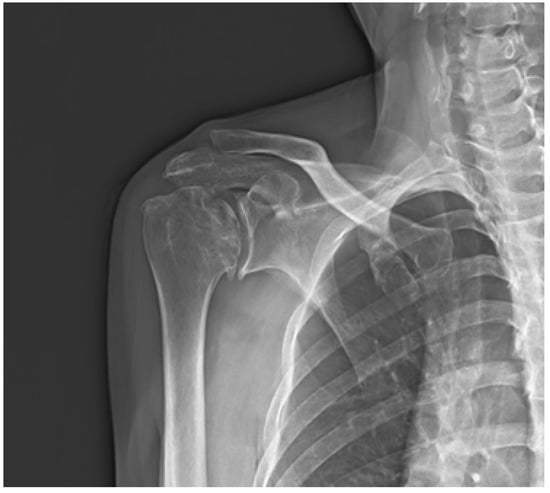

Figure 3.

(A). Immediate postoperative anteroposterior radiograph. (B). Anteroposterior radiograph of the shoulder 6 months post-operation showed no significant change in the radiographic findings of the glenohumeral joint.